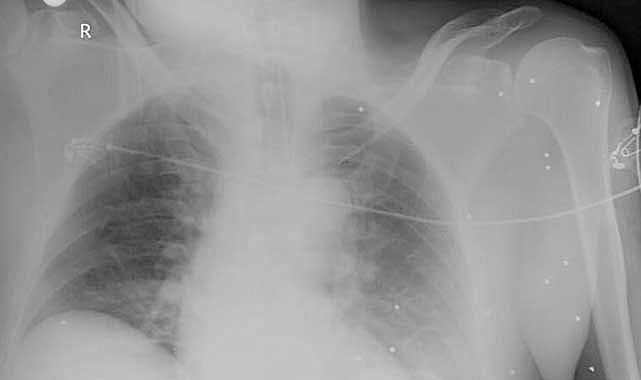

Antalya'nın Serik ilçesinde eski Abdurrahmanlar Mahallesi Muhtarı Tuncer Yıldırım (52), kredi ve miras yüzünden husumetli olduğu ağabeyi Osman Yıldırım'a (59) av tüfeğiyle ateş etti. Ağır yaralanan Yıldırım'ın vücudunda, 300'e yakın saçma tespit edildi.